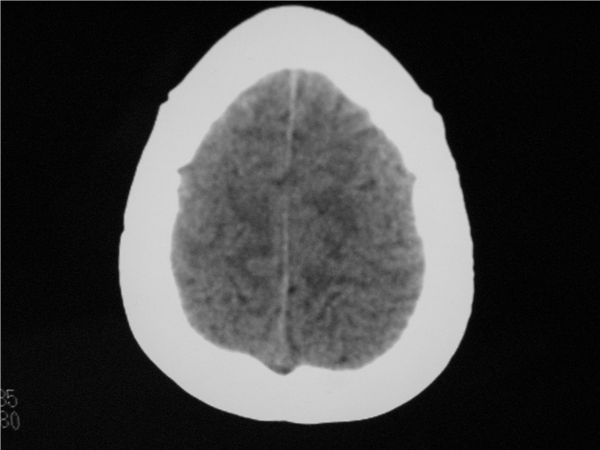

以下是引用随光逐影在2009-8-1 14:17:00的发言:[br]透明隔囊肿与vergae腔并存。

以下是引用zjzjr在2009-8-1 14:51:00的发言:[br]五、六脑室形成。